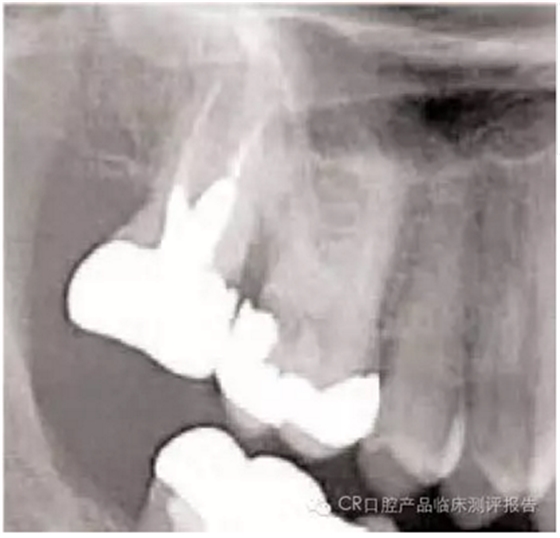

● 影像學(xué)檢查的要點

- 包括根尖:注意根尖的形狀(喇叭口、彎曲、融合、球形),有些情況需要牙根縱切。

- 找出牙根附近重要組織的影像:牙周膜(PDL)的缺口、上頜竇、血管神經(jīng)、高密度骨質(zhì)區(qū)域。根內(nèi)是否含有根管?(觀察比較難因為根管易碎或與骨長合)

4. 在不觸碰鄰牙的前提下,牙根不在上頜竇內(nèi)的情況下(需拍x線片確認(rèn),放置根間有竇腔),可以用702車針將復(fù)雜牙齒的腭根和頰根分開。